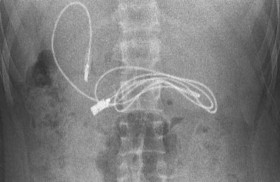

سلك شاحن في معدة مراهق

صدم مراهق الأطباء، بعد نقله إلى أحد مستشفيات تركيا وهو يعاني من غثيان شديد وآلام مبرحة في معدته، إذ أظهرت الأشعة المقطعية، ابتلاعه سلك شاحن طوله 90 صنتيمتراً. وخضع المراهق الذي لم تكشف ... إقرأ المزيد